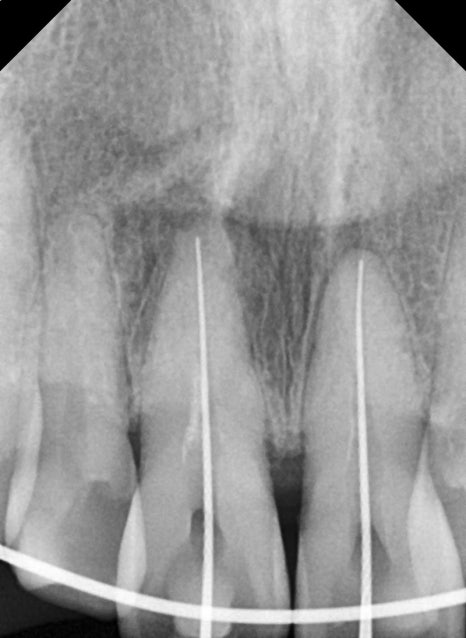

회복 기간 이후 앞니 신경치료까지

강한 충격을 받은 치아는

몇 주~몇 달 뒤 시림, 통증, 변색이 발생할 수 있습니다.

이는 신경 손상 때문입니다.

환자분도 앞니 두 개에서 신경 괴사 가능성이

확인되어 정확한 근관장 측정 후

신경치료가 진행되었습니다.

신경치료가 정확히 이루어지지 않으면 향후

치근단염이나 재신경치료가 필요할 수 있어,

앞니 외상에서는 “지켜보자”보다

적기에 치료하는 것이 안전합니다.